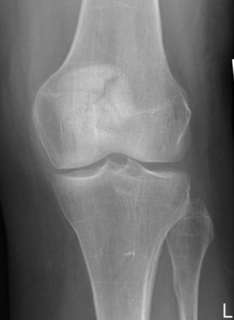

What type of fracture is this?

Butterfly -comminuted